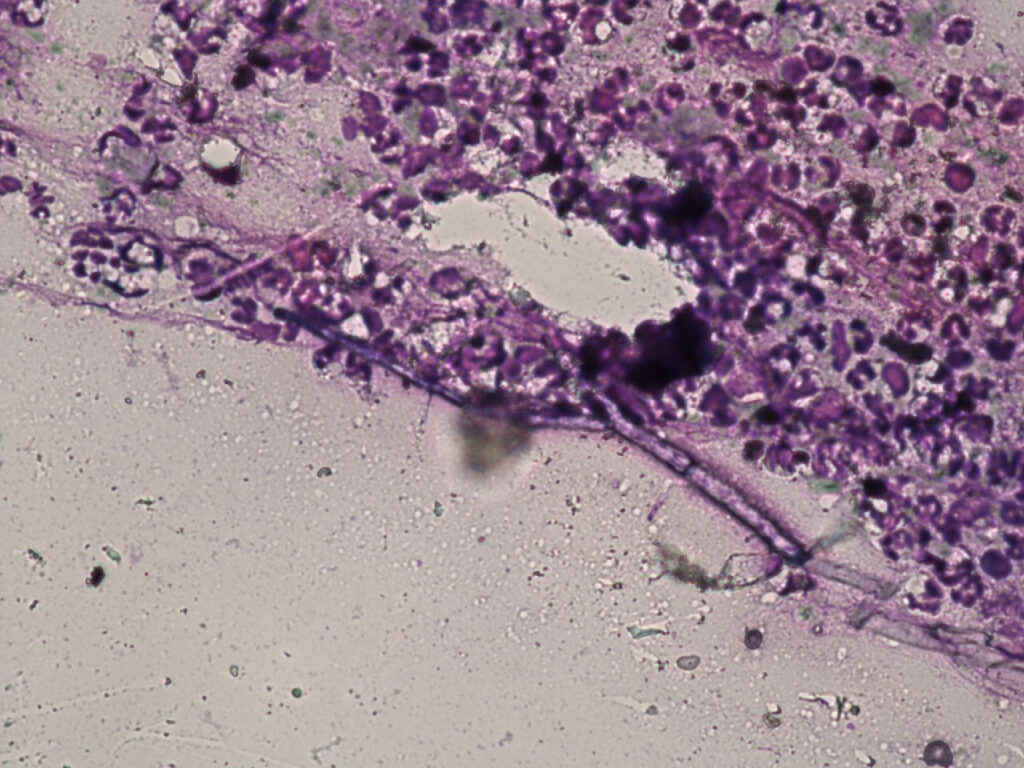

Abb. 3: Zytologie eines Ausstriches aus der Nasenhöhle eines Hundes zeigt Pilzhyphen, 40er Vergrößerung

Bildquelle: Laboklin

In manchen Fällen sind zytologische Präparate für eine erste Einschätzung geeignet. Bei nasalen Mykosen und bei Neoplasien können zytologische Ausstriche aus repräsentativen Arealen für eine Diagnosestellung ausreichend sein (Abb. 3). Es ist jedoch zu beachten, dass bei negativen Befunden kein Ausschluss dieser Differenzialdiagnosen möglich ist. Für die Bestimmung der Tumorentität ist eine histologische Untersuchung unabdingbar.